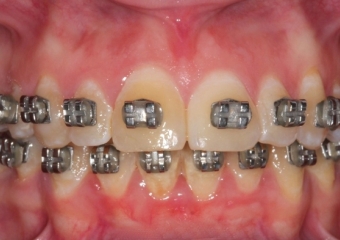

Mordida inicial